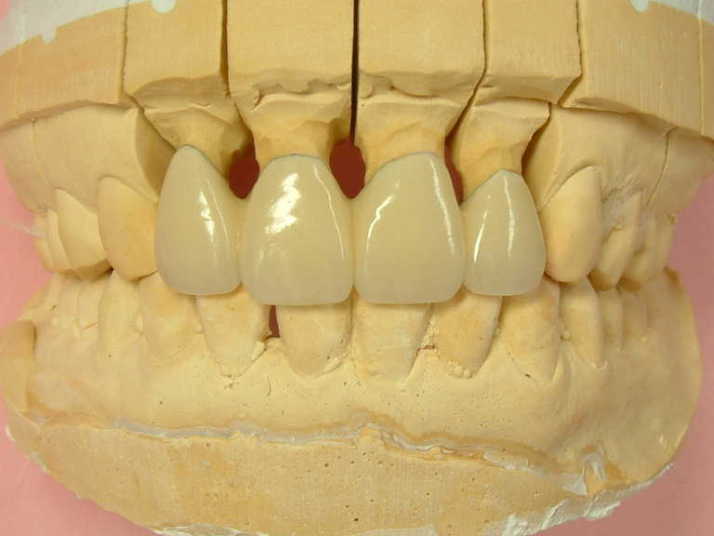

補綴物物 完成

患者さんから「出っ歯にならないよに!」

と再度念を押されたので

出来る限り内側に入れて製作しました。

模型上では、1.1下部孤形空隙が広いように

見えますが、歯肉模型にて調整して

歯肉を圧迫せず、息が漏れることが無いように

調整しました |